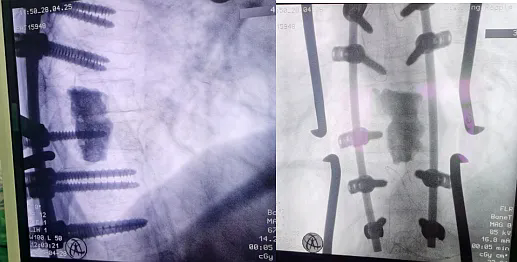

自述胸背痛已有2个月,来诊前近7小时症状加重并伴有双下肢麻木无力。经检查发现,患者胸背部有明显叩痛,双下肢肌力为0级,腱反射消失,大小便不能自主控制。胸椎MRI和CT检查提示胸9-10椎体及附件异常信号影(图1),椎管内脊髓受压严重,同时双肺CT发现右肺占位(图2),考虑为脊柱转移瘤。

图3

术前,为患者进行了包括补液、抗心律失常治疗等术前准备,以改善心脏功能,降低手术风险。术中,医护团队对病变椎体进行了部分切除,解除了脊髓的压迫,并使用骨水泥进行了充分隔离。同时,对病变椎体上下各两个节段进行了钉棒固定(图3),以确保脊柱的稳定性。